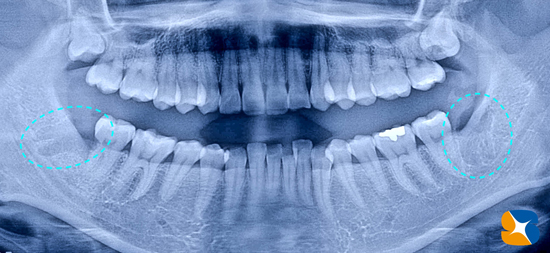

60代の超・怖がり(歯科恐怖症)の女性。これは、当院で7年前に治療を終えた時の写真。本日の主訴は「右下の歯茎が腫れてきて、入れ歯が痛くて入らない。」でした。

健康な時の歯茎の様子

レントゲンでチェックすると、横向きの親知らずの歯が存在することが確認できます。